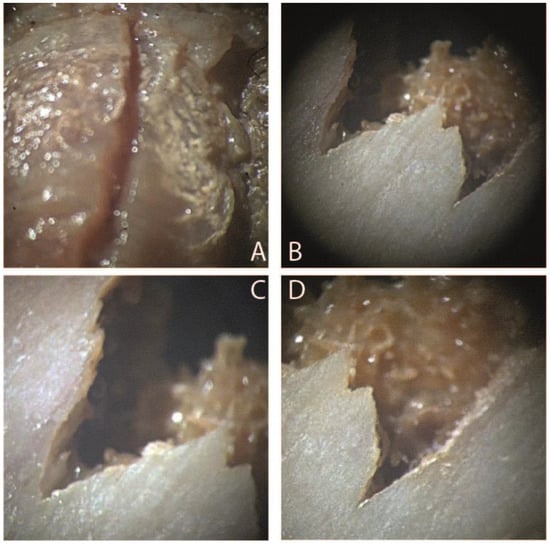

2.4. Stereomicroscope

In the laboratory, the bones were cleaned first by brushing and then washed with water with sieving of the water used for washing to avoid losing any valuable finds. Subsequently, bone fragments of the most significant interest were observed through a stereomicroscope(Carl Zeiss A772415, Carl Zeiss Co., Oberkochen, Germany) to determine the presence or absence of cut mark characteristics. In case 1,the lesion at the level of the intervertebral disc of the III vertebra appears linear, with an accumulation of tissue adjacent to the lesion and perfectly compatible with a stab lesion of a depth of 4 mm. The lesions at the level of the iliac crest present a “V” shape, a classic form of stabbing lesions(Figure 4). In case 2, the color variations of the charred remains were assessed using the Munsell, HEX, and RGB color scales to extrapolate the different exposure temperatures. The femur diaphysis, the cranium, and the long bones showed the typical changes of burned bones at stereomicroscopy analysis: color changes, fissuring, cracking, fractures, delamination of the cortical bone (Figure 5).

Figure 4. View of bone lesions with stereomicroscopy (Carl Zeiss A772415, CarlZeiss Co., Oberkochen, Germany) of case 1 (scale bar 5:1). (A) Lesion at the level of the III lumbar vertebra (zoom ×3.2). It appears linear, with clean margins, perfectly referable to the action of a blade; (B) lesions at the level of the iliac wing (zoom ×3.2). The classic ‘V’ shape and sharp margins can be seen. (C,D) Detail of the “V” shape (zoom ×3.6).